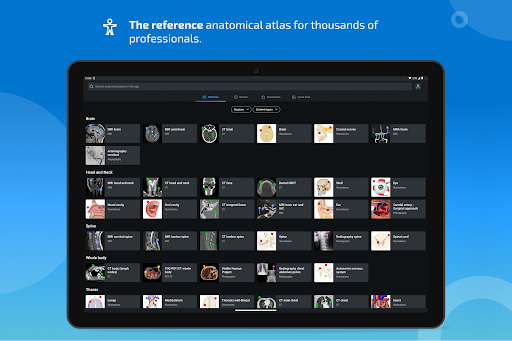

e-Anatomy tiene más de 26 000 imágenes que contienen series de imágenes en vistas axiales, coronales y sagitales, así como radiografías, angiografías, imágenes de disección, gráficos anatómicos e ilustraciones. Todas las imágenes médicas fueron etiquetadas cuidadosamente, más de 967 000 etiquetas disponibles en 12 idiomas, incluida la Terminologia Anatomica latina.

- Seleccione las etiquetas anatómicas por categoría